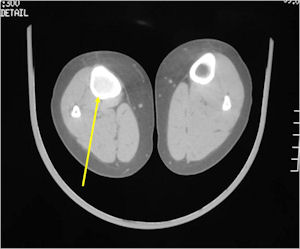

CT Scan:

- Well defined nidus with a smooth peripheral margin; +/- mineralization (CT more sensitive than XR and MRI for detecting mineralization); CT is better for detecting nidus in presence of exuberant sclerosis